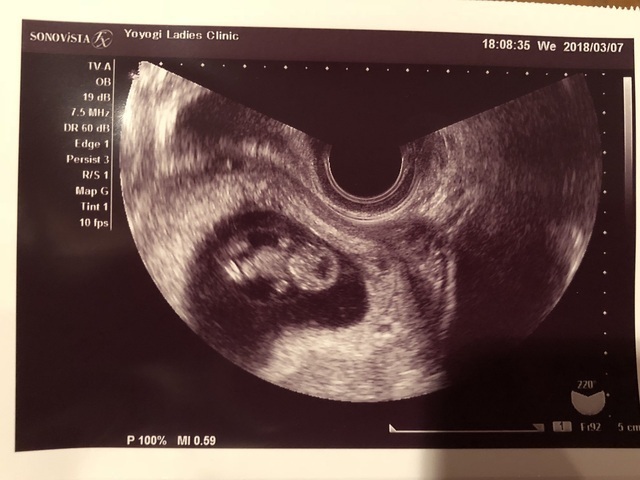

9週6日(9w6d・男の子)|右京りお さん(27歳)

エコー写真撮影時のエピソード:

不妊治療をずっとしていて、ようやく授かれた我が子。心拍確認しても、まだなんだか実感がわかなくて。そんなとき三回目の検診で小さな小人のような、我が子がエコーでうつりました。

一ヶ月前は形をなしてなかったのに横顔がはっきりとわかるように。自然とエコー画面を、指先で愛しく撫でてしまいました……ああ、この子が我が子なのだなと思うと涙がこぼれたのをよく覚えています。